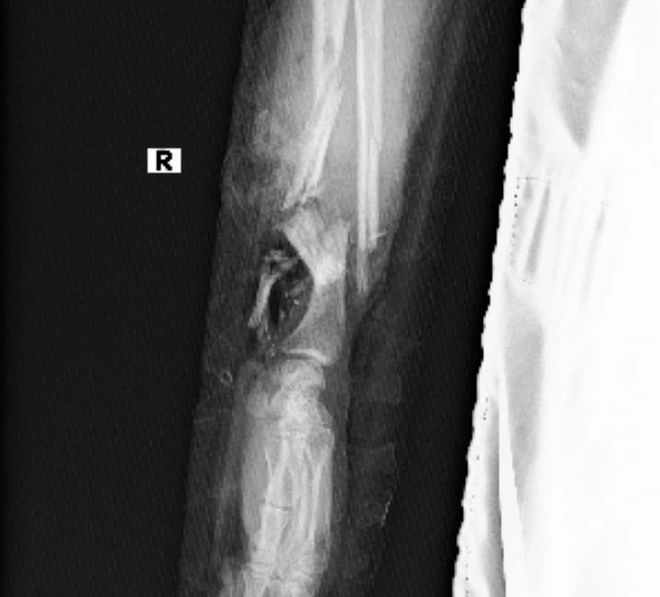

Ảnh chụp X-Quang và hình ảnh bàn tay được nối vào chân nữ bệnh nhân thời điểm ca phẫu thuật thành công

Trước nguyện vọng đó, các bác sĩ đã đưa ra quyết định khó khăn nhưng đầy tính nhân văn là sẽ tiến hành bảo tồn bàn tay đứt lìa bằng cách ghép tạm thời vào cẳng chân (P), kèm nối mạch vi phẫu, che phủ đầu gần cẳng tay vào vạt da ngẫu nhiên vùng bụng, nhằm duy trì tuần hoàn máu và giữ nguyên cấu trúc mô trong thời gian chờ nối lại tay vào thời điểm thích hợp hơn.